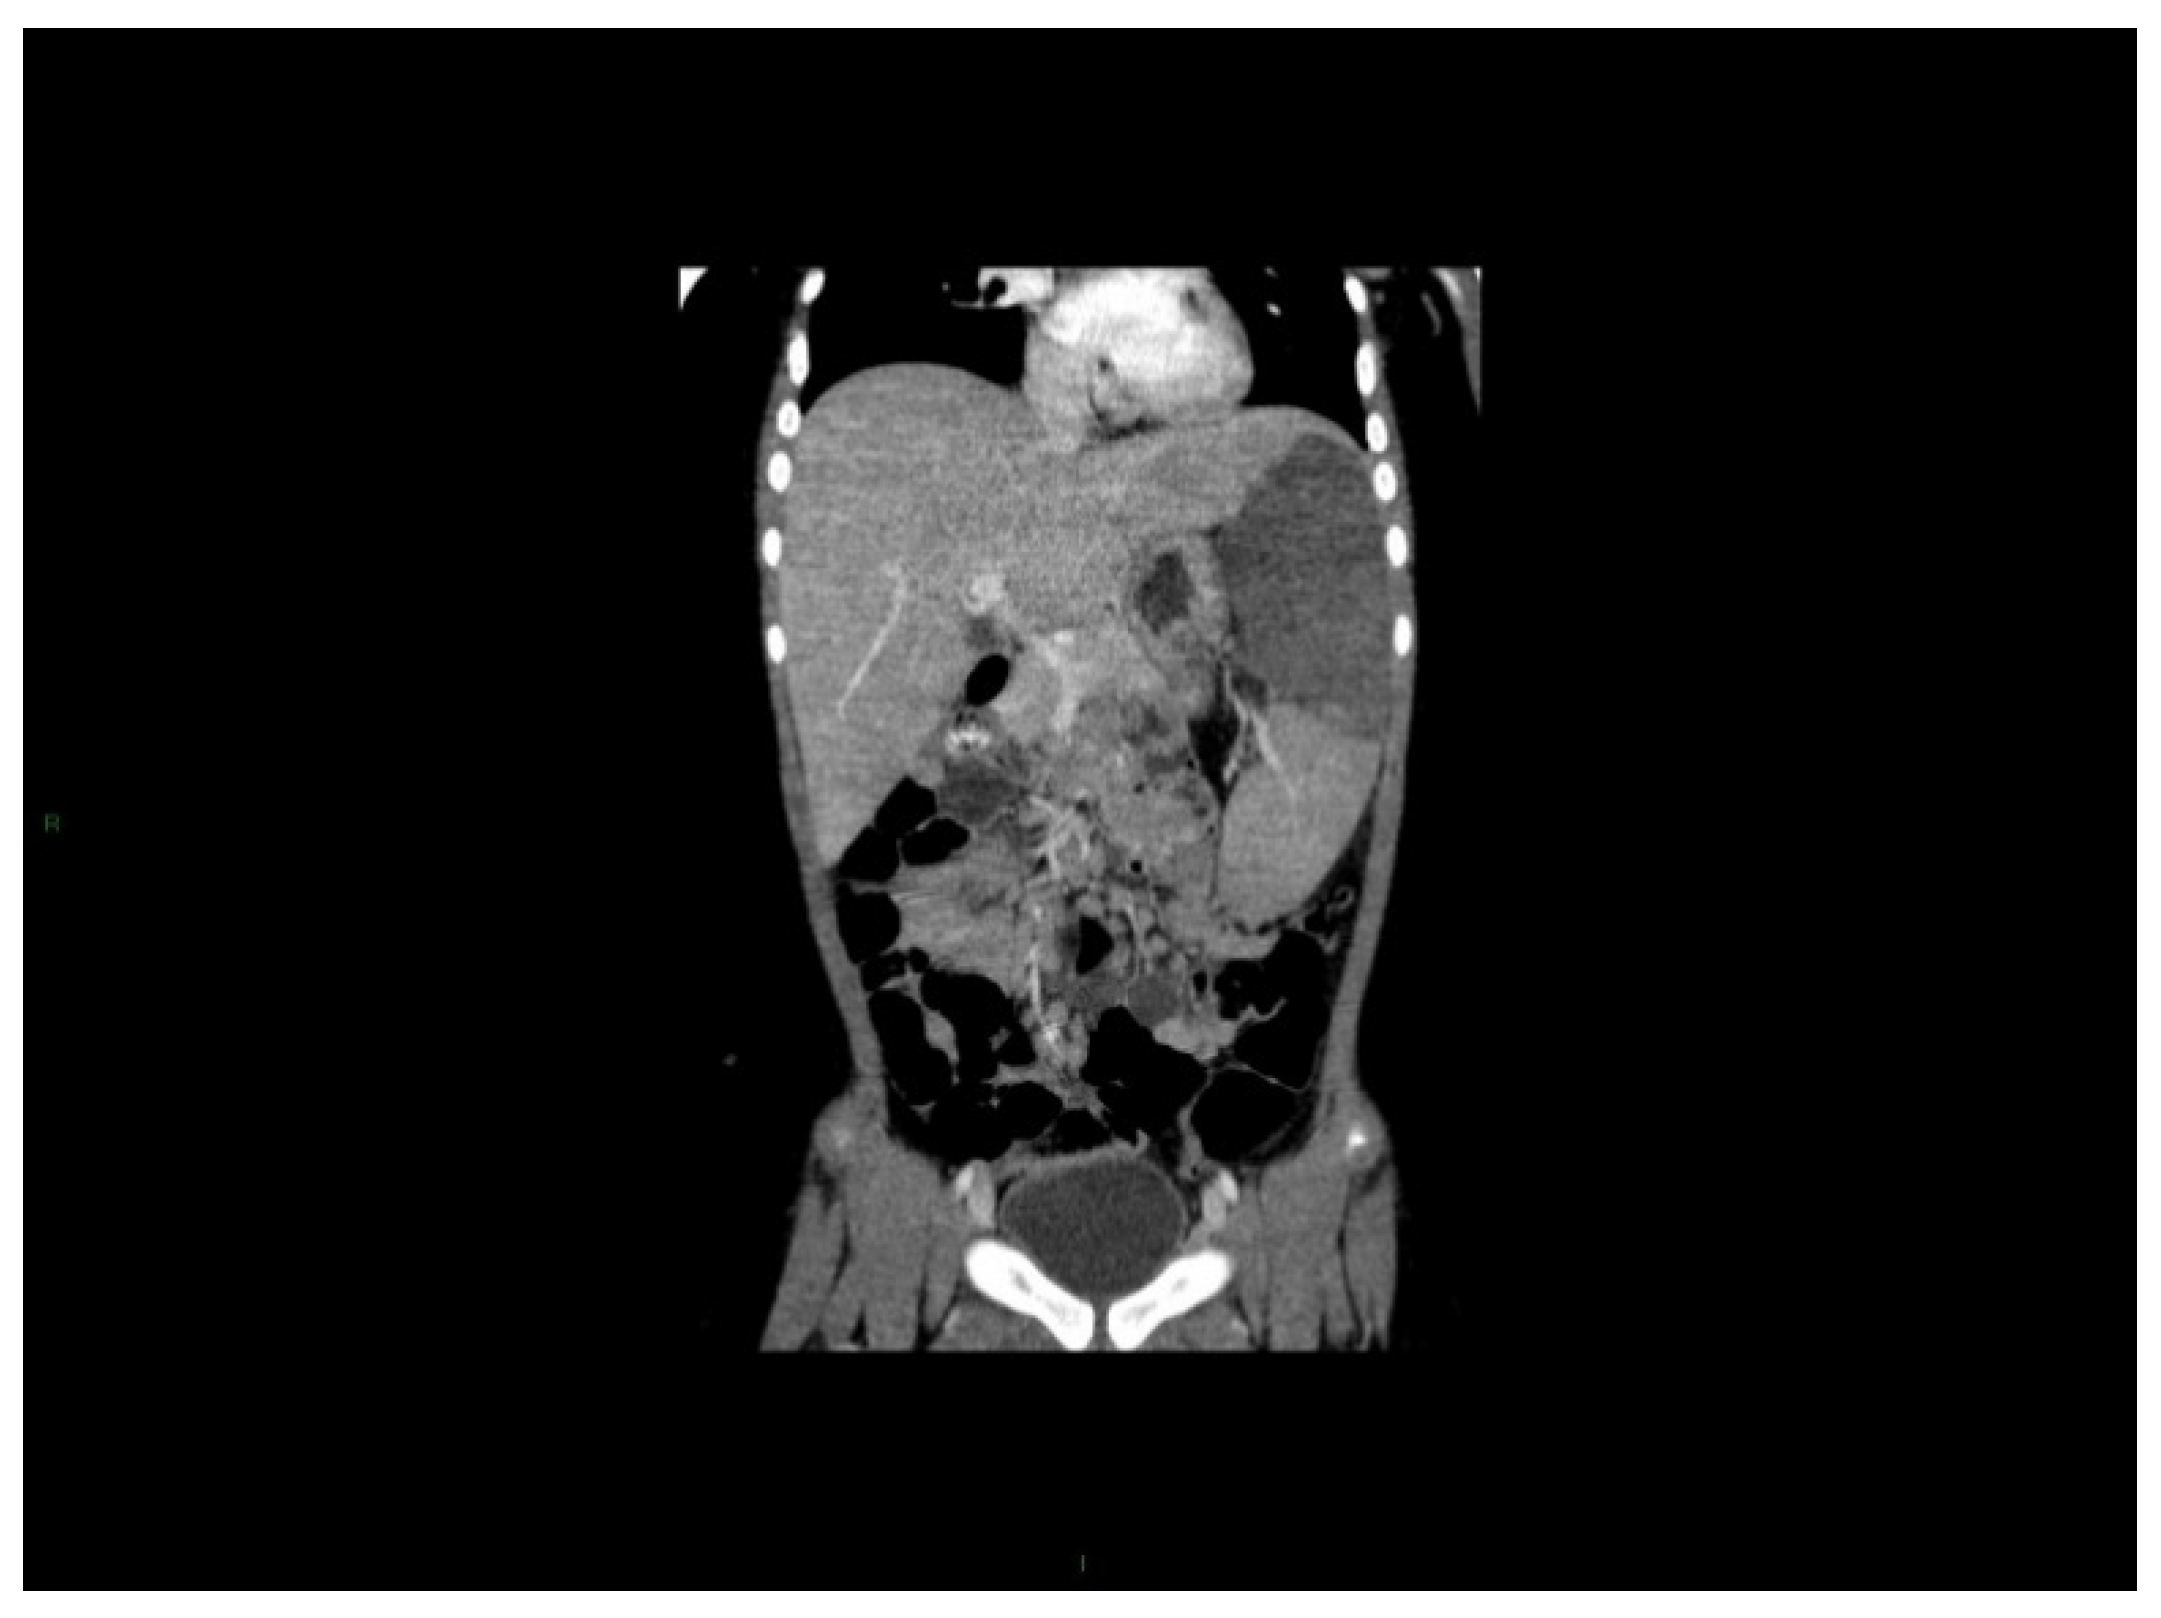

- spleen size, liver size (both in cm below the costal margin) on quiet breathing,

- Giagounidis, A.A.; Burk, M.; Meckenstock, G.; Koch, A.J.; Schneider, W. Pathologic rupture of the spleen in hematologic malignancies: Two additional cases. Ann. Hematol. 1996, 73, 297–302. [Google Scholar] [CrossRef] [PubMed]

- Drummond, D.; Lenoir, M.; Petit, A.Y. Splenic infarction in a child revealing chronic myeloid leukemia. Eur. J. Pediatr. 2012, 171, 1141–1142. [Google Scholar] [CrossRef] [PubMed]